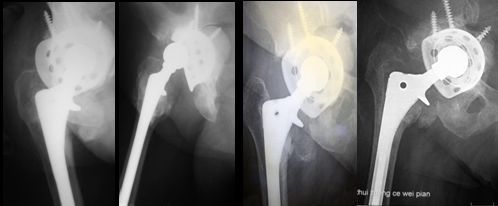

45岁,女性患者,2010年4、5月前于外院行分别行双侧全髋关节置换术,术后1年开始出现双髋轻微疼痛,未予系统诊治;2014年3月来我院就诊,只能卧床,被动强迫体位,双髋活动严重受限,X片如上。

诊断为双侧人工髋关节假体周围感染,于2014年4月分别行双侧髋关节假体取出、病灶清理、抗生素骨水泥占位器旷置术

感染控制后于2014年7月、8月分别行左、右侧复杂髋关节翻修术(Spcer占位器取出,钛网固定、打压植骨、翻修假体植入,右侧联合使用大粗隆钢板)。术后4年复查照片如上,打压植骨血管化,髋关节假体稳定,位置角度良好,患者功能恢复良好。